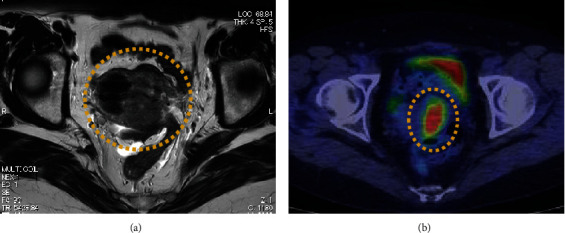

从生殖器外部位转移到子宫的情况非常罕见。我们介绍了一例女性病例,她曾接受过小肠癌手术,随后出现左侧卵巢和子宫转移。一名 50 多岁的无子宫妇女因患小肠癌接受了腹腔镜小肠部分切除术和淋巴结清扫术。五个月后,计算机断层扫描(CT)发现左侧卵巢肿瘤和腹水。她接受了双侧附件切除术和辅助化疗,卵巢肿瘤被诊断为小肠癌转移。小肠癌手术两年后,正电子发射断层扫描(PET)-CT 扫描发现子宫积液。宫颈细胞学检查未发现上皮内病变或恶性肿瘤。子宫内膜组织学检查显示为子宫腺癌。患者接受了全腹子宫切除术,随后接受了辅助化疗。子宫肿瘤的组织病理学和免疫组化结果显示,这是一种小肠癌转移瘤(细胞角蛋白7 [CK7] [-]、细胞角蛋白20 [CK20] [+]、特殊AT-富序列结合蛋白2 [SATB2] [+]、配对盒基因2 [PAX2] [-]和雌激素受体[ER] [-])。对于癌症患者来说,组织病理学和免疫组化对于区分原发性和转移性肿瘤以及指导治疗方案的选择非常重要。

Uterine metastases from extragenital sites are rare. We present a case of a woman who had undergone surgery for small intestinal cancer and subsequently developed metastases in her left ovary and uterus. A nulliparous woman in her 50s underwent laparoscopic partial small bowel resection with lymph node dissection for small intestinal cancer. Five months later, computed tomography (CT) revealed a left ovarian tumor and ascites. She underwent bilateral adnexectomy and adjuvant chemotherapy, and the ovarian tumor was diagnosed as a small intestinal cancer metastasis. Two years after the small intestinal cancer surgery, a positron emission tomography (PET)-CT scan revealed a uterine accumulation. Cervical cytology was negative for intraepithelial lesion or malignancy. Endometrial histology showed an adenocarcinoma of the uterus. The patient underwent total abdominal hysterectomy followed by adjuvant chemotherapy. Histopathology and immunohistochemistry of the uterine tumor revealed that it was a metastasis of small intestinal cancer (Cytokeratin 7 [CK7] [-], Cytokeratin 20 [CK20] [+], Special AT-Rich Sequence-Binding Protein 2 [SATB2] [+], Paired Box Gene 2 [PAX2] [-], and estrogen receptor [ER] [-]). In patients with cancer, histopathology and immunohistochemistry are important for distinguishing between primary and metastatic tumors and for guiding the choice of treatment.